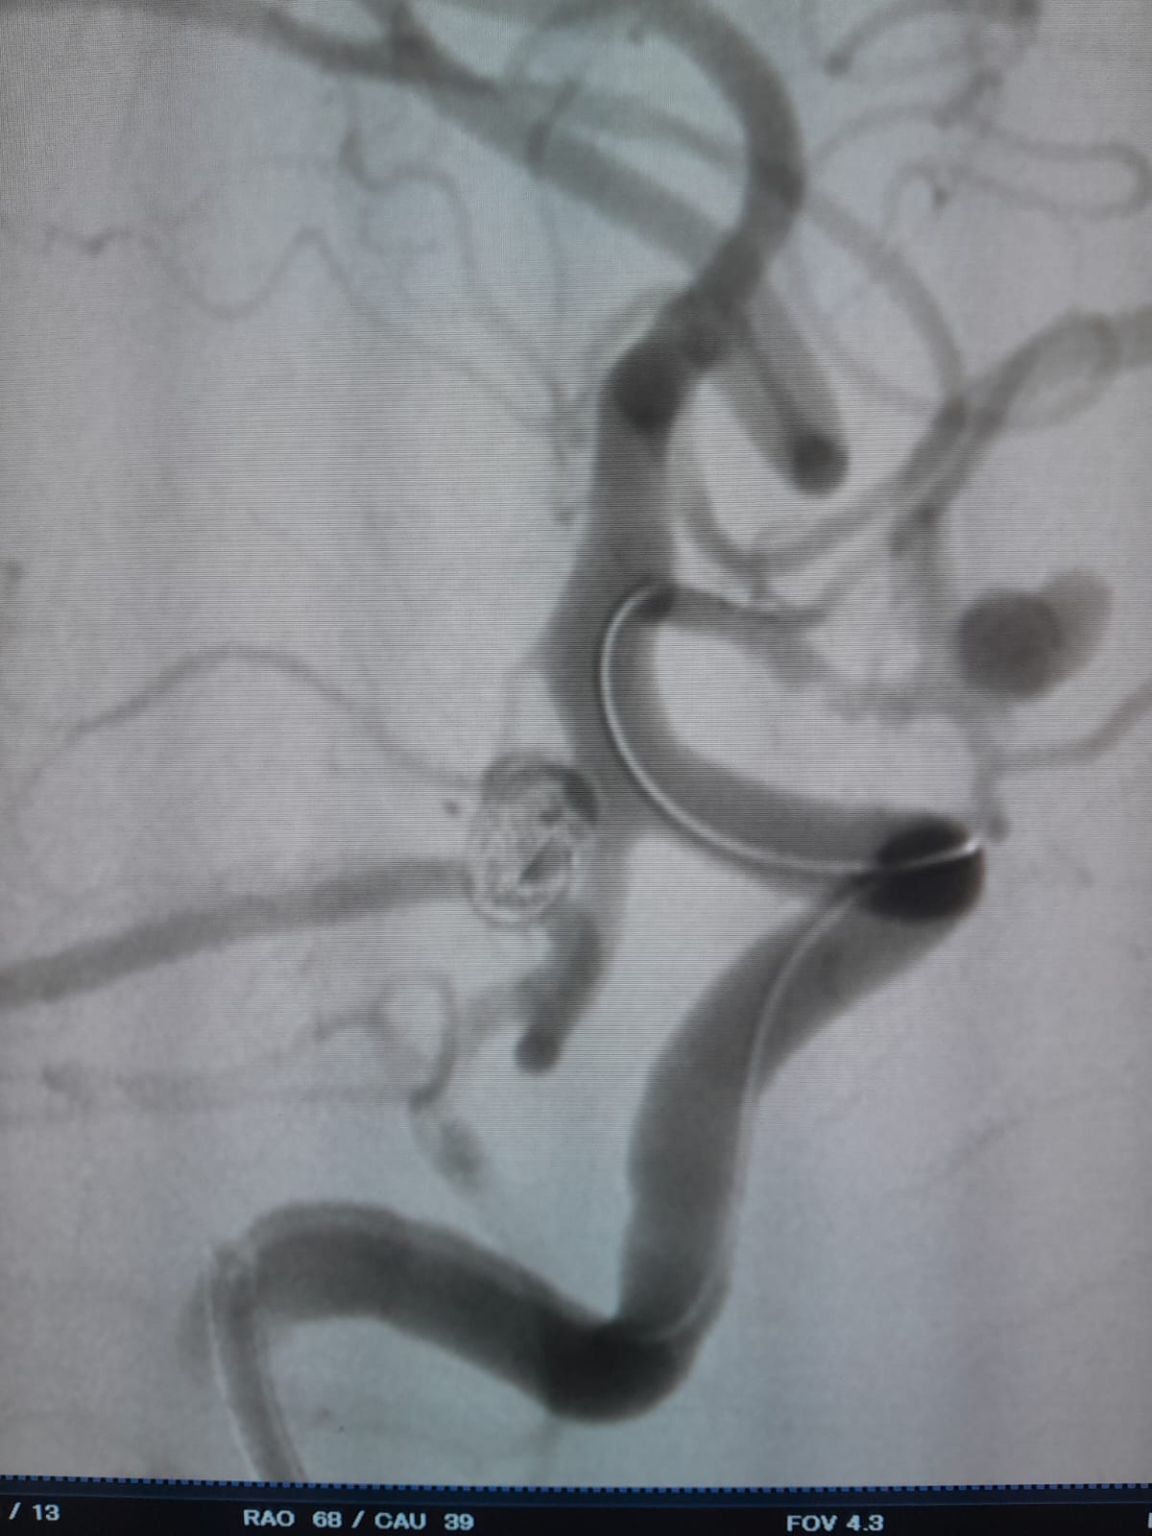

During follow-up, residual filling was noted in the previously treated posterior communicating artery aneurysm. The team re-accessed the site using Frepass® Disposable Microcatheter (TJMC18 Plus) and successfully deployed a Nuva® Flow Diverter (TJED-D-4.5-16), which demonstrated ideal wall apposition and excellent flow diversion, leading to highly satisfactory treatment outcomes.